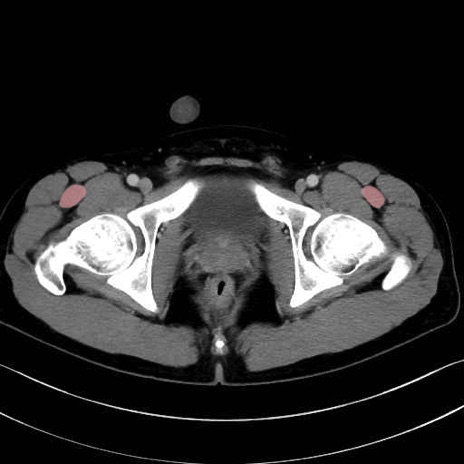

大腿筋膜張筋 (Tensor fasciae latae)